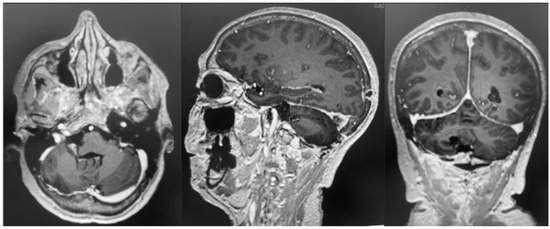

After admission, the patient underwent a cerebral MRI, which showed a huge extra-axial lesion in the posterior cranial fossa (5 × 4.4 × 4.3 cm). The lesion demonstrated low SI on T1 and intermediate SI on T2 and avidly enhancing post-Gad administration. The mass showed no restriction on DWI. The mass was broad-based on the right tentorium cerebelli with a discrete supratentorial extension, compressing the adjacent right cerebellar hemisphere, the cerebellar peduncle, the brainstem, the IV ventricle, and the right occipital lobe. A characteristic dural tail sign was demonstrated on post-Gad sequences (Figure 1).

Figure 1. Preoperative MRI + C: a posterior fossa extra-axial mass was demonstrated, showing a low SI on T1 and intermediate SI on T2, which avidly enhanced post-Gad administration. The mass was broad-based on the right tentorium cerebelli with a discrete supratentorial extension, thus compressing the adjacent right cerebellar hemisphere, the brainstem, the IV ventricle, and the right occipital lobe.